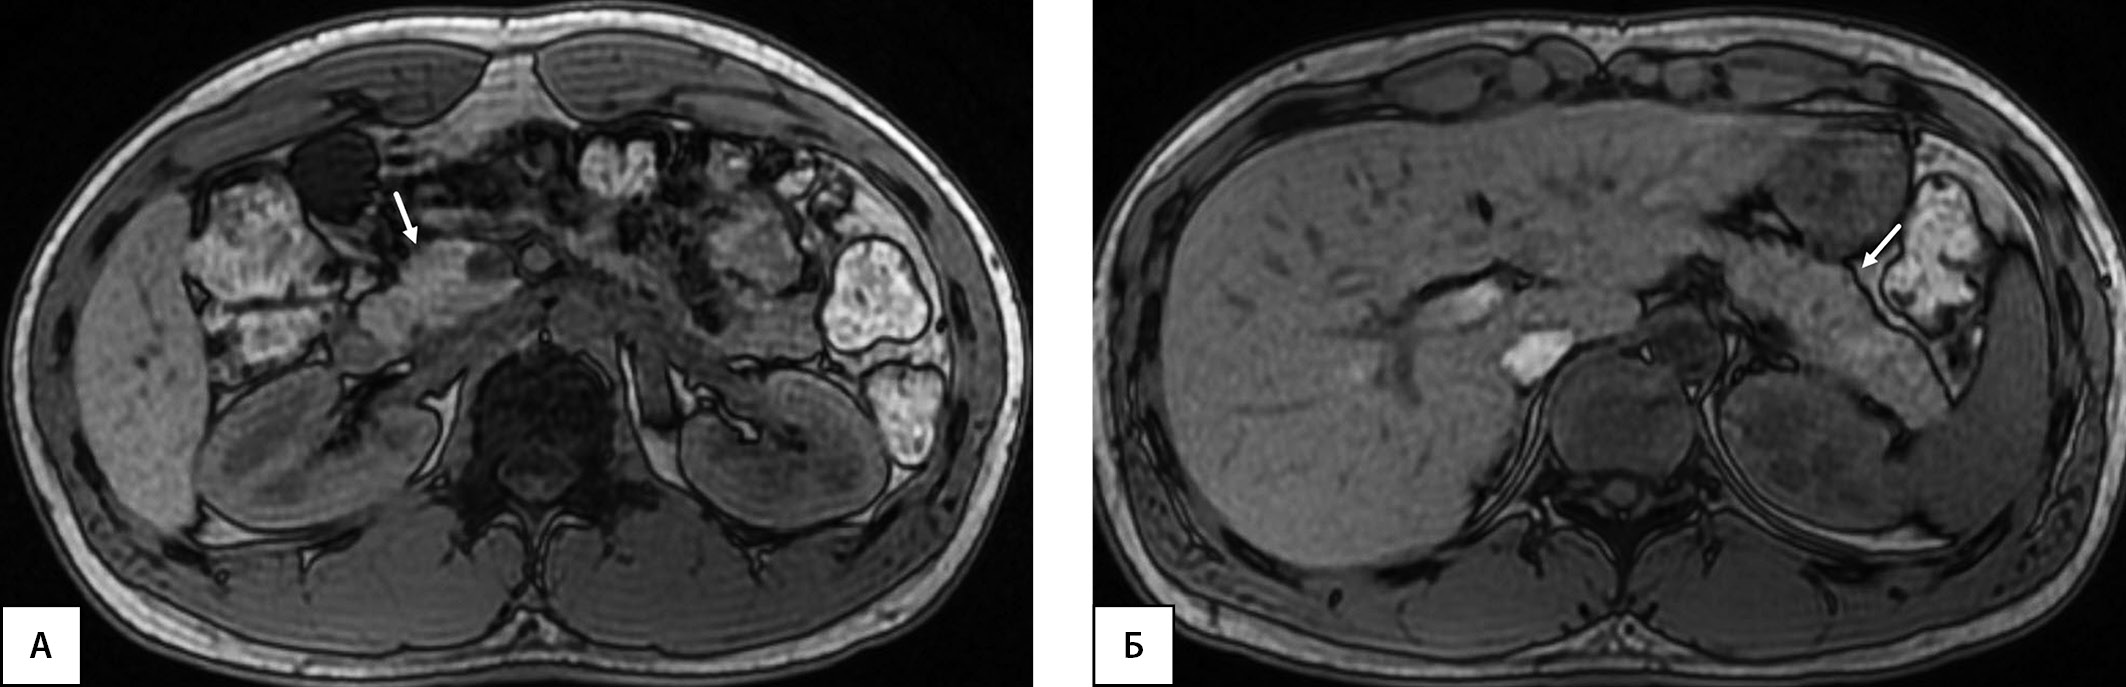

Рисунок 1. Пациент, 19 лет (длительность СД1 — 17 лет). МРТ органов брюшной полости на уровне головки поджелудочной железы (А, В) и на уровне тела и хвоста (Б, Г). А, Б — Т2-ВИ, аксиальная плоскость; В, Г — Т1-ВИ, аксиальная плоскость. Определяется диффузное снижение объема поджелудочной железы, более выражены изменения на уровне головки (стрелки). ОПЖ=15,2 мл; ОПЖ/ИМТ=15,2/22,98=0,66 мл/(кг/м2); ОПЖ/ППТ=15,2/1,89=8,04 мл/м2.

Примечание. ОПЖ — объем поджелудочной железы. ИМТ — индекс массы тела. ППТ — площадь поверхности тела. ВИ — взвешенные изображения.